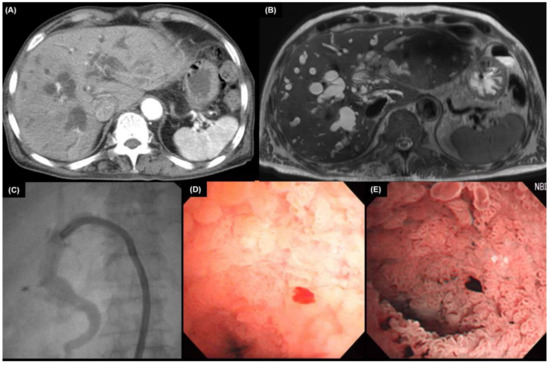

4.2. Multidetector Computed Tomography

4.2.1. Intrahepatic Cholangiocarcinoma

4.2.2. Extrahepatic Cholangiocarcinoma

5. Endoscopic Findings

5.1. Cholangiography

6. Pathologic Findings